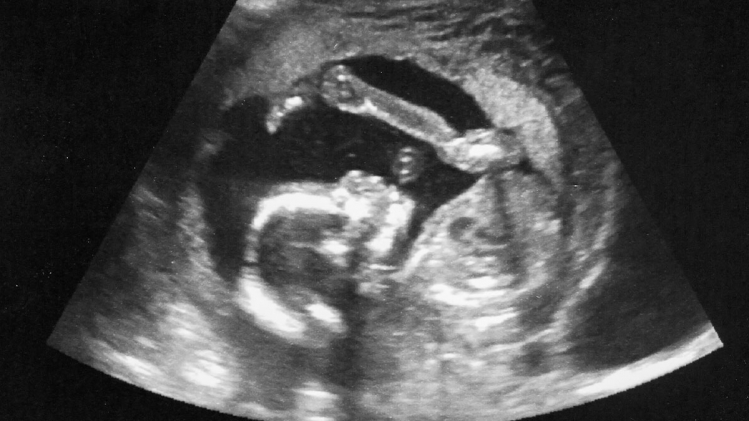

L'intelligence artificielle (IA) est capable de détecter des anomalies foetales près de deux fois plus rapidement que la technologie actuelle, selon les résultats d'un essai britannique publié jeudi.

Mené sur 78 femmes enceintes, avec l'aide de 58 échographistes, cet essai, le premier du genre, a été mené par des chercheurs du King's College de Londres, en partenariat avec la fondation de l'hôpital Saint Thomas.

Il a montré que les échographies réalisées avec l'aide de l'IA étaient 42% plus rapides que les échographies classiques.

L'essai s'est concentré sur la recherche de problèmes cardiaques dans les échographies réalisées lors de la 20e semaine de grossesse, même si les chercheurs ont indiqué que l'IA pouvait rechercher toute anomalie foetale. "Notre recherche a montré que les échographies réalisées avec l'IA sont précises, fiables et plus efficaces", a déclaré l'auteur principal de l'étude, le docteur Thomas Day.

Selon lui, la technologie permet de se passer des temps de pause dont les échographistes ont besoin afin de mesurer et d'enregistrer les images pendant leur examen médical. "Nous espérons qu'utiliser l'IA dans ces échographies permettra de libérer du temps précieux pour les échographistes afin qu'ils puissent se concentrer sur les soins aux patients, rendant l'expérience plus confortable et rassurante pour les parents", a-t-il ajouté.

Ashleigh Louison était l'une des femmes enceintes impliquées dans l'essai. L'échographie réalisée avec l'IA a détecté une maladie cardiaque chez son fils à naître, Lennox. "Recevoir un diagnostic précoce pour Lennox était vraiment important, car cela signifiait que nous pouvions correctement planifier le chemin vers l'avenir", a-t-elle déclaré, citée dans le communiqué de l'étude.